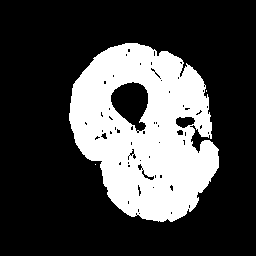

(b)

Finally, we define the set of corrected pseudo-labels as the intersection between the and masks. Examples are shown in Fig. 2.

Inspired by source-free domain adaptation approaches [8], we argue that the feature within the same category should lie closer to their class prototypes, enforcing a high correlation for samples of the same class. In the case of segmentation, image regions with highly correlated voxels in feature space often have compact intensity ranges [18]. Thus, instead of estimating the distance of a pixel to different class prototypes [13], we directly exploit the class prototype information hidden in the intensity distribution of a set of given regions. As the intensity values of the thigh muscle are mostly distributed in the range of after normalizing the input images () to the range , we extract coarse masks that exclude most of the IMF tissue. A single coarse mask is denoted as: